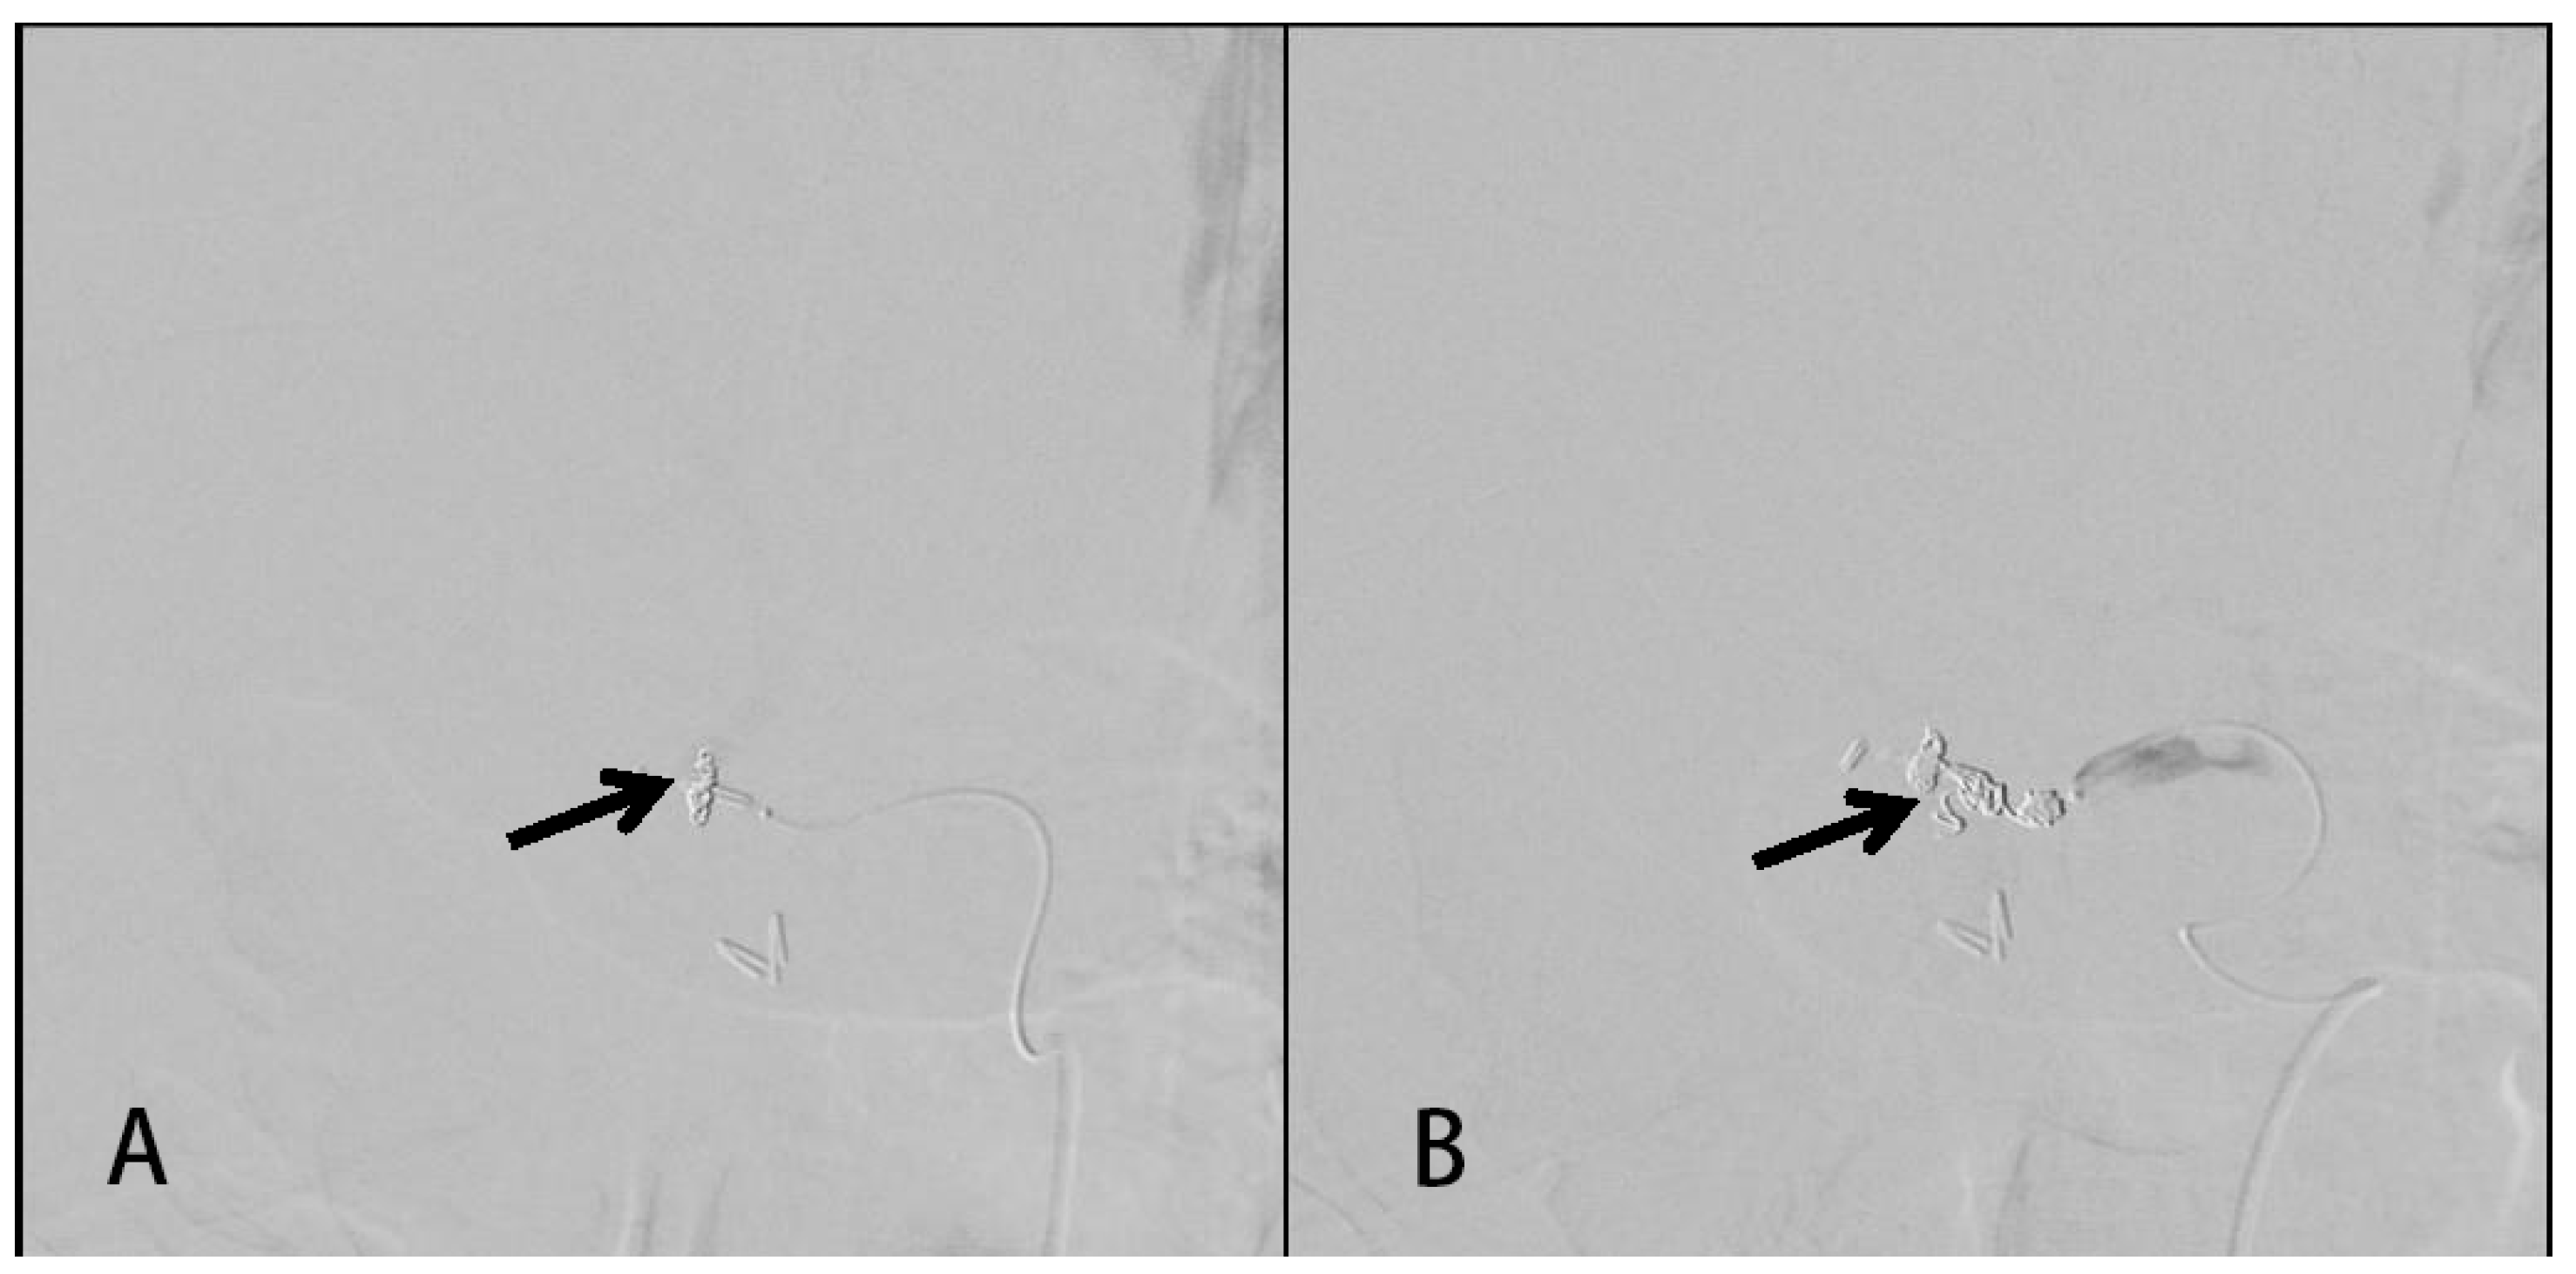

2. Detailed Case Description